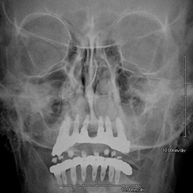

- Mandibular X-ray

This technique uses X-ray rendered imaging for examining the jaw. Indicated for: trauma, congenital anomalies.